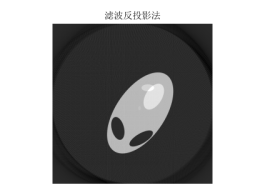

图 9

图 10

图 11

由滤波公式与原来灰度像素矩阵每一列进行卷积,得到了消除边缘失锐的灰度像素矩阵再用原本未滤波的模型进行图形重建运算,程序见附录程序四,结果以及效果如下:

图 14

图 15

图 16